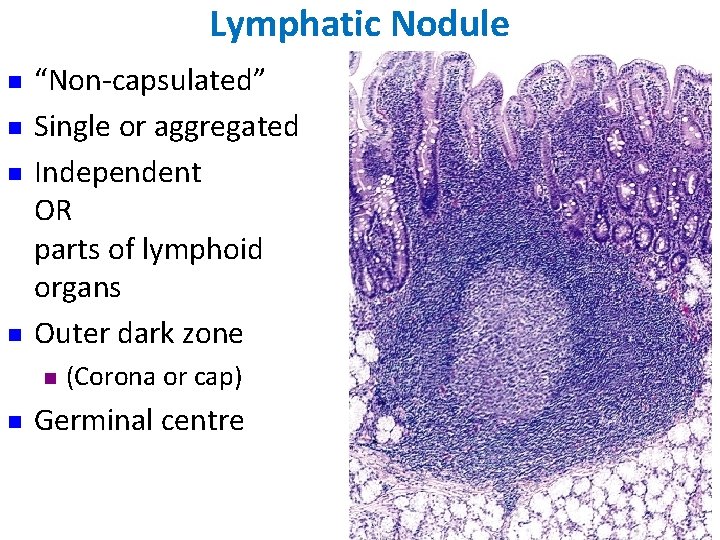

Lymphoid Nodules (Follicles): These occur in all lymphatic aggregates except the thymus. Active (lymphocyte-producing) nodules each have a darkstaining periphery, or mantle zone, that contains tightly packed small lymphocytes, and a light-staining core, or germinal center, that contains numerous immunoblasts (lymphoblasts), ie, lymphocytes stimulated by antigens to enlarge and proliferate. The lighter staining reflects the increased cytoplasmic volume and decreased nuclear heterochromatin that accompany lymphocyte activation.

Lymphatic Nodule n n “Non-capsulated” Single or aggregated Independent OR parts of lymphoid organs Outer dark zone n n (Corona or cap) Germinal centre